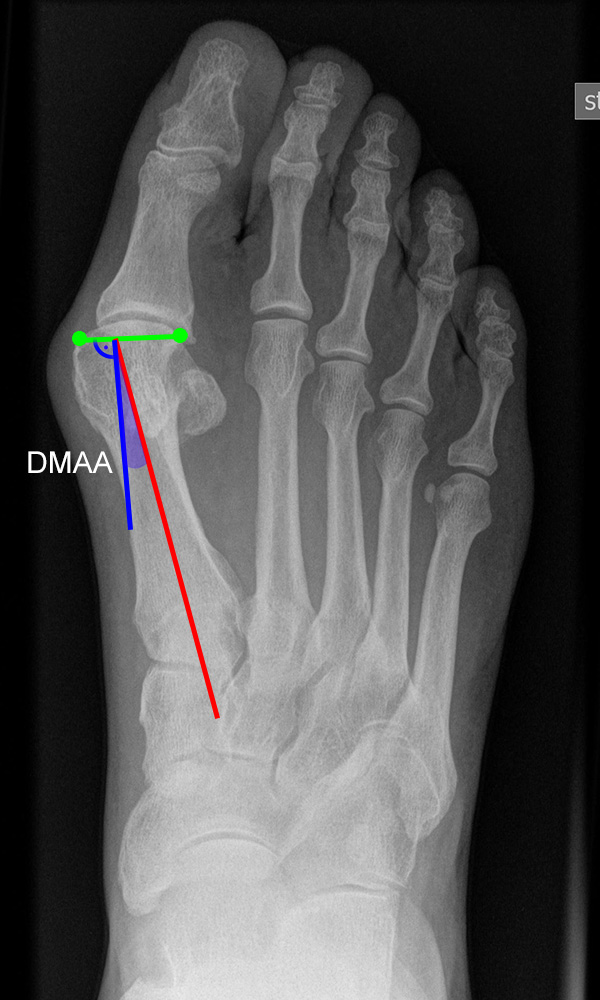

Vermessung der belasteten Aufnahmen des Fußes

Winkelmessungen am Fußskelett beziehen sich sämtlich auf belastete Aufnahmen 6. Die folgenden Aufnahmen zeigen die üblicherweise verwendeten Winkelmaße und ihre Definition. Viele Fehlstellungen des Fußes betreffen den Vor- und Rückfuß. Dies sollte bei der Beurteilung der Bilder und der Therapieplanung stets berücksichtigt werden.

Beurteilung von Fehlstellungen des Vorfußes

Zur Vollansicht und zum Lesen der Bildbeschreibung bitte die Bilder anklicken.

Gelenkflächenwinkel

DMAA (Distal metatarsal artikular angle, Syn. Gelenkflächenwinkel): Winkel zwischen der Achse des Os metatarsale I (rot) und dem Lot auf die distale Gelenkflächenebene (blau) des Os metatarsale I. Die Gelenkflächenebene (grün) wird definiert durch zwei Punkte, welche die mediale und laterale Begrenzung der Gelenkfläche definieren (Norm: <10° 5). Die Projektion des DMAA ist stark abhängig von der Rotation des Os metatarsale I 7. Daher ist bei der operativen Behandlung des Hallux valgus eine Beurteilung häufig erst nach Korrektur der Pronationsstellung des Os metatarsale I möglich. Tendenziell wird der DMAA auf präoperativen Röntgenaufnahmen überschätzt.